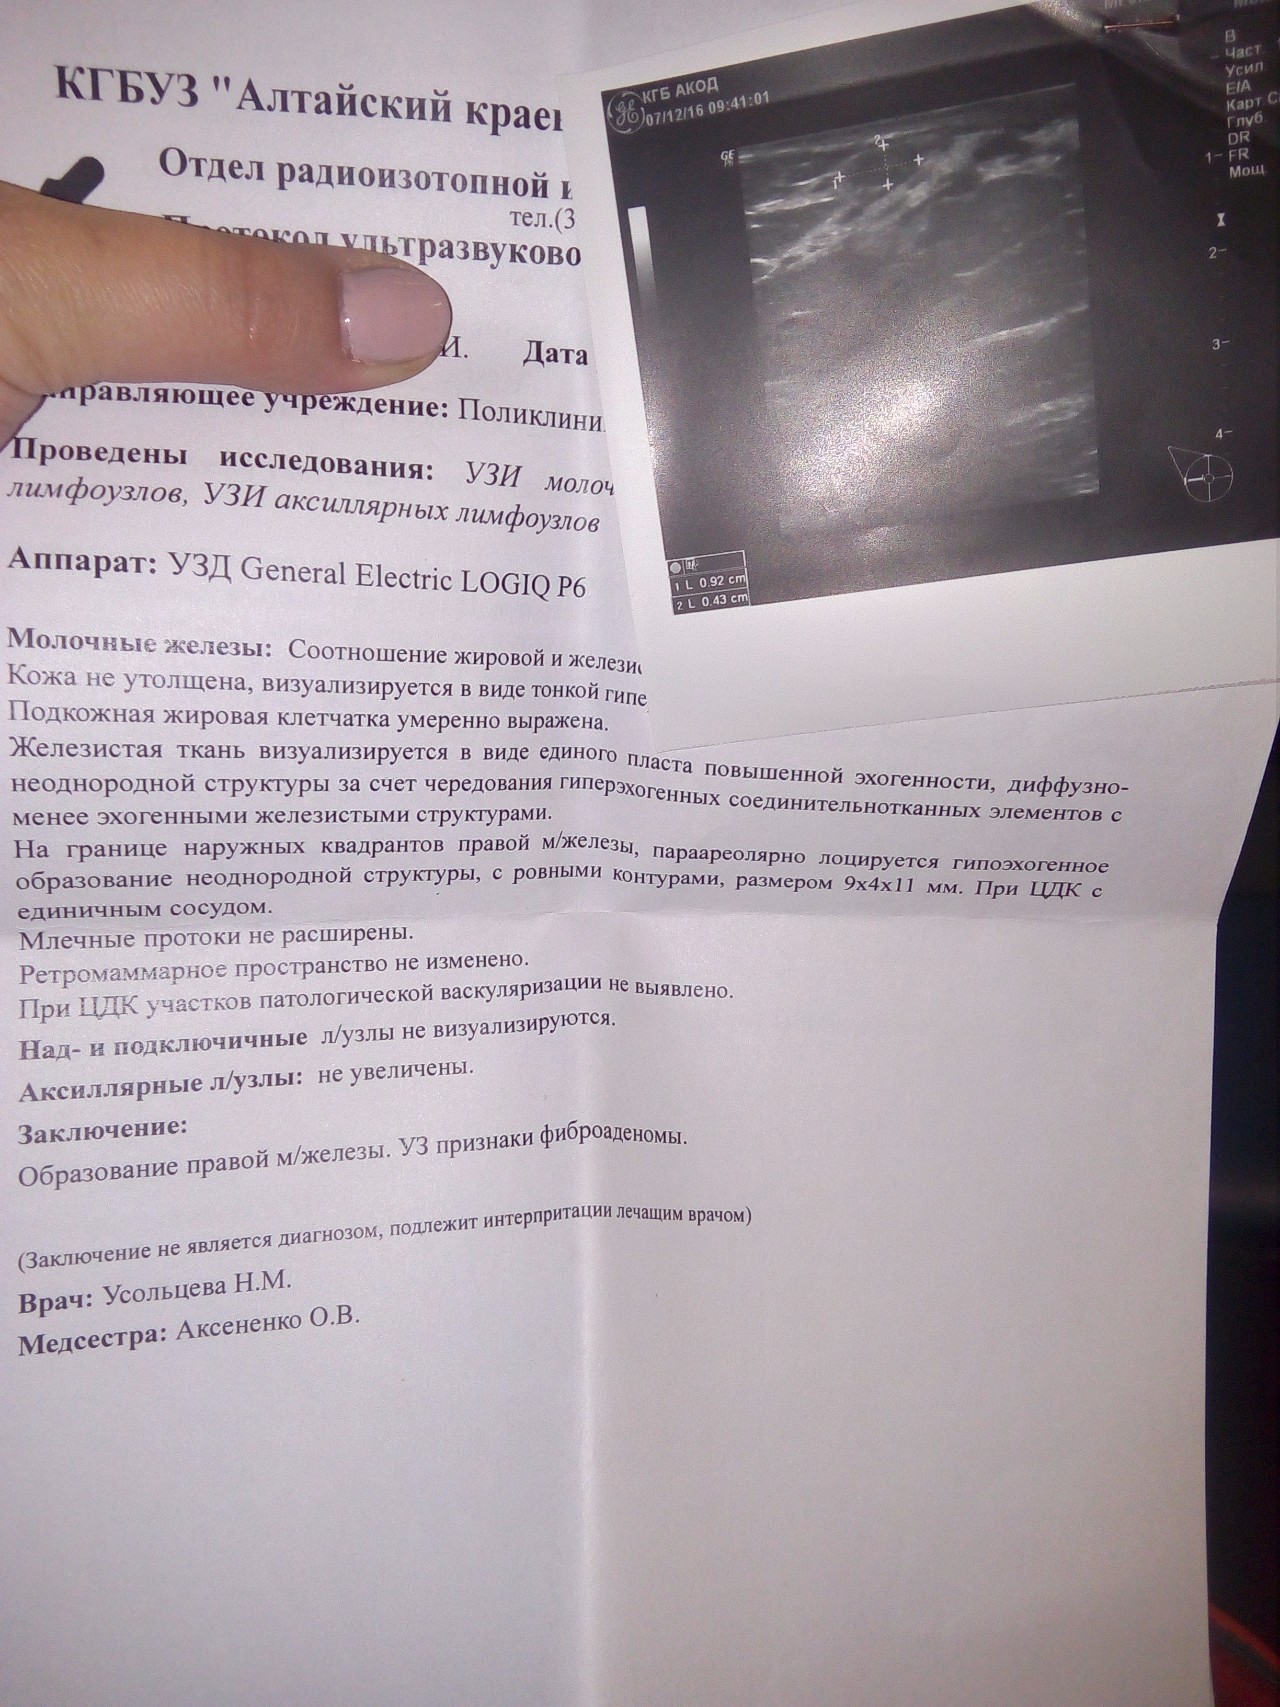

Фиброаденома молочной железы - доброкачественное образование, которое часто встречается у женщин. Оно может быть обнаружено при помощи различных методов диагностики, включая маммографию. Ниже представлены фотографии, помогающие понять, как выглядит данное заболевание.

Маммография и ее роль в диагностике фиброаденомы молочной железы

Маммография - это рентгенологическое исследование молочных желез. Оно позволяет выявить различные изменения в тканях, включая фиброаденому. На маммограммах можно увидеть структурные особенности опухоли и отследить ее динамику во времени.